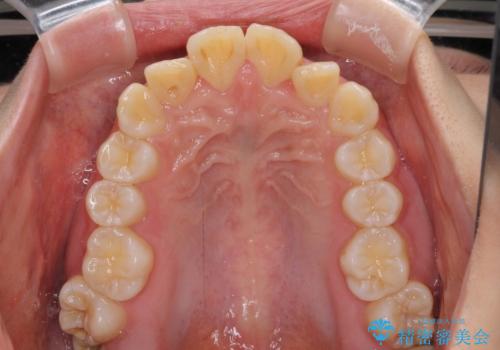

【モニター】出っ歯と八重歯 抜歯矯正でスッキリとした口元に

- 前方に飛び出した前歯と、下顎の八重歯を気にして来院された患者様です。

口元の突出感を改善するため、上下左右の第一小臼歯4本を抜歯し、ワイヤー装置にて矯正治療を行うこととしました。

抜歯矯正により、口元の印象だけでなく、横顔の印象も大きく改善されました。